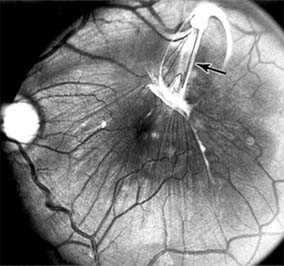

Figure 10-3

Figure 10-3: Fluorescein angiogram of central serous chorioretinopathy shows active disease with both a retinal pigment epithelial detachment (small arrows) and a sensory retinal detachment (large arrows). Two foci of inactive disease (open arrows) are also present.

The diagnosis is made by slitlamp examination of the fundus; the presence of serous detachment of the sensory retina in the absence of ocular inflammation, subretinal neovascularization, an optic pit, or a choroidal tumor is diagnostic. The retinal pigment epithelial lesion appears as a small, round or oval, yellowish-gray spot that is variable in size and may be difficult to detect without the aid of fluorescein angiography. Fluorescein dye leaking from the choriocapillaris may accumulate below the pigment epithelium or sensory retina, resulting in a variety of patterns including the well-recognized smokestack configuration.